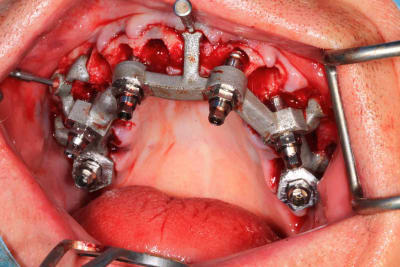

Le cas N°2 en images reelles :)

Guide métal avec support clavette, os assez fin : il est prévu un sticky bone complet : donc : lambeau avant extraction, positionnement du guide base et forage des clavettes, positionnement du guide implant, pose des piliers MU, controle des axes prothétique avec le guide pilier, collage des piliers prov sur le bridge a armature métal, occlusion nickel, sticky bone et PRF, sutures suspendues.

T’as quand même une sacrée déviation des implants / à la planification…..

Ça se voit déjà avec les implants posés à travers le guide de forage métallique qui est amha trop permissif

Et c’est confirmé par ton guide pour les piliers multiunits qui n’est même pas à fond (clavette antérieur pas mise….enfin certainement impossible à mettre)

Mais tu as raison, il y avait un peu trop de jeu au niveau du guide .

C’est le premier entièrement métallique que je fais imprimer ( Fridentech ). Il faut que je fasse un modèle avec plusieurs diamètres pour avoir le meilleur ajustage . Je pense que le mieux serait d’insérer une douille ETK. C’est ce que fait Dimitri avec ses guides métalliques codiagnostic.